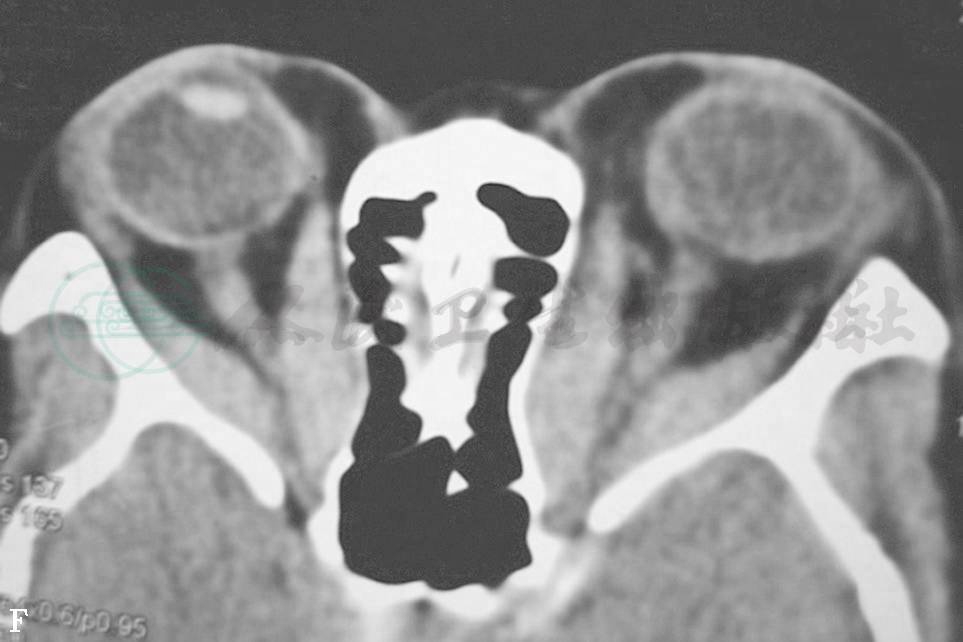

CT扫描均显示眼球突出的原因分为3种:①眶内脂肪含量增加,而眼外肌无明显增大(图3A、B);②眶内脂肪含量增加,眼外肌也增大(图3C、D);③眶内脂肪含量增加不明显,眼外肌增大明显(图3E、F)。

图3眼球突出

A.双眼球明显突出 B.眼眶CT轴位扫描见眼眶脂肪明显增多,眼外肌未增大 C.双眼球突出、呈上转位 D.眼眶CT轴位扫描见眼眶脂肪增多、眼外肌增大 E.双眼球突出 F.CT轴位扫描见眼外肌明显增大,眼眶脂肪不增多